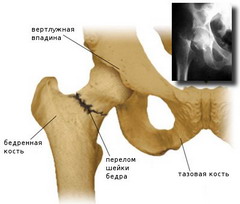

Головка бедренной кости покоится на верхнем проксимальном эпифизе, соединяясь с остальной костью с помощью шейки, отстоящей от оси тела бедренной кости под углом 114-153 градуса. У женщин, благодаря большей ширине таза, угол наклона шейки бедренной кости приближается к прямому.

Переломом бедренной кости называется состояние, характеризующееся нарушением ее анатомической целостности. Чаще всего, оно случается у пожилых людей, при падении на бок. Сопутствующими факторами переломов бедра в этих случаях являются сниженный тонус мышц, а также остеопороз.

Признаками перелома являются резкая боль, отечность, нарушение функции и деформация конечности. Вертельные переломы характеризуются более интенсивными болями, которые усиливаются при попытке движения и ощупывании. Основной признак перелома верхней части (шейки) бедра – «симптом прилипшей пятки» – состояние, при котором пациент не может повернуть ногу под прямым углом.